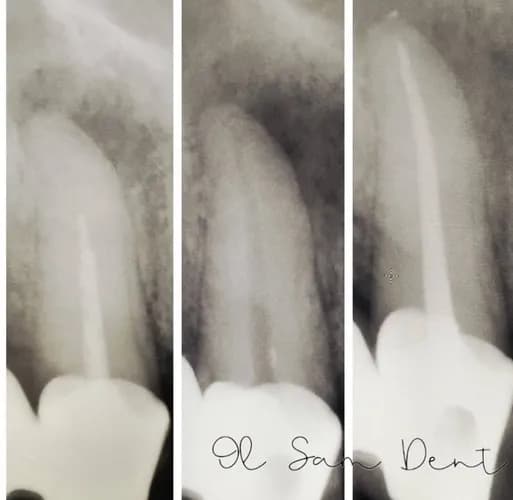

Прицільний знімок зуба у Варшаві - це ваш рятувальний круг у такій ситуації. За кілька секунд рентген показує все приховане: чи запалився нерв, чи є кіста на верхівці кореня, чи не тріснув зуб під старою пломбою. Без цього знімка лікар працює навмаця, а з ним - ставить точний діагноз і планує лікування, яке дійсно допоможе, а не просто заглушить біль на день. Це швидко, безпечно і дає чітку відповідь: лікуємо чи видаляємо.